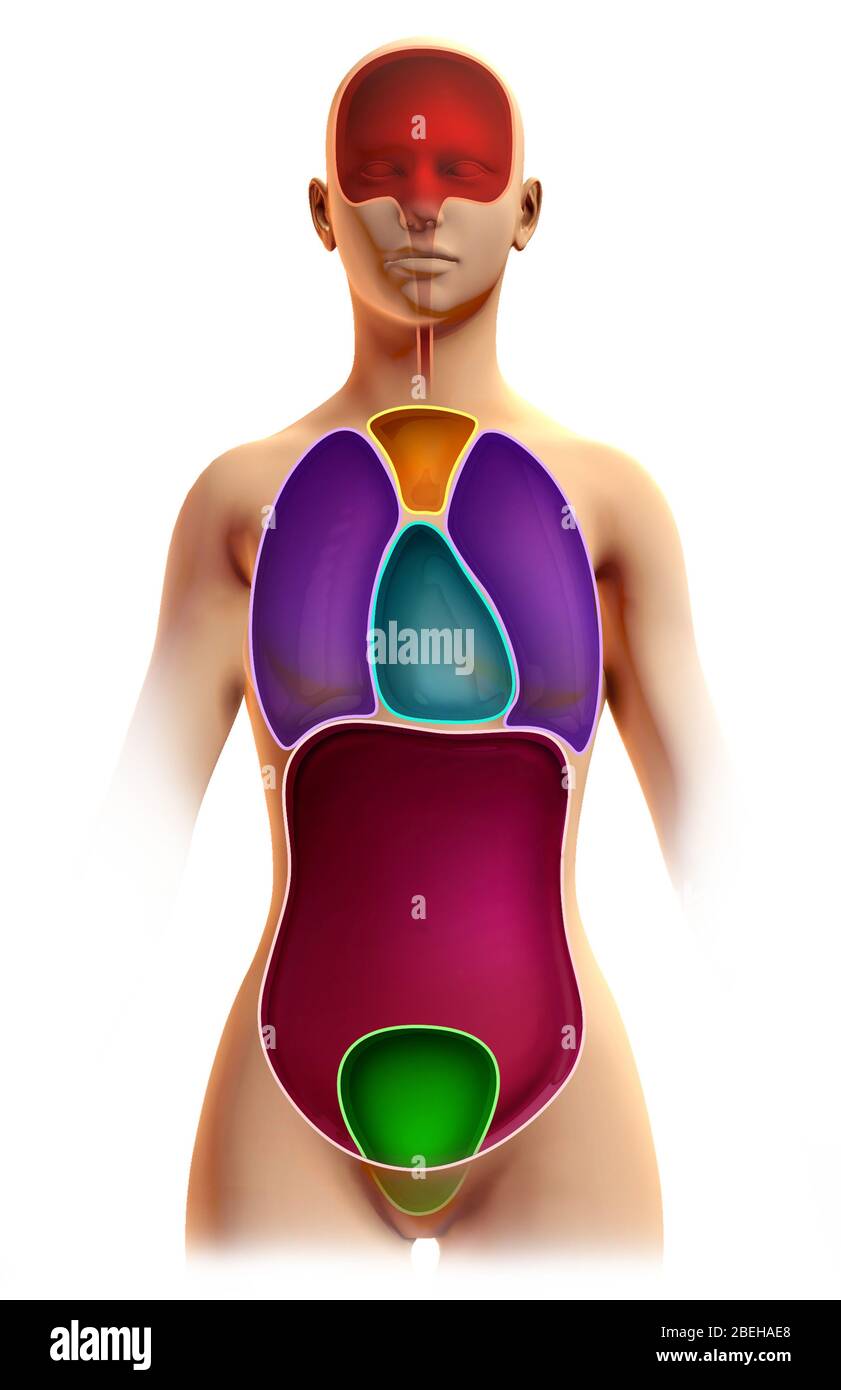

Cavités du corps, illustration Banque D'Imageshttps://www.alamyimages.fr/image-license-details/?v=1https://www.alamyimages.fr/cavites-du-corps-illustration-image353193968.html

Cavités du corps, illustration Banque D'Imageshttps://www.alamyimages.fr/image-license-details/?v=1https://www.alamyimages.fr/cavites-du-corps-illustration-image353193968.htmlRM2BEHAE8–Cavités du corps, illustration